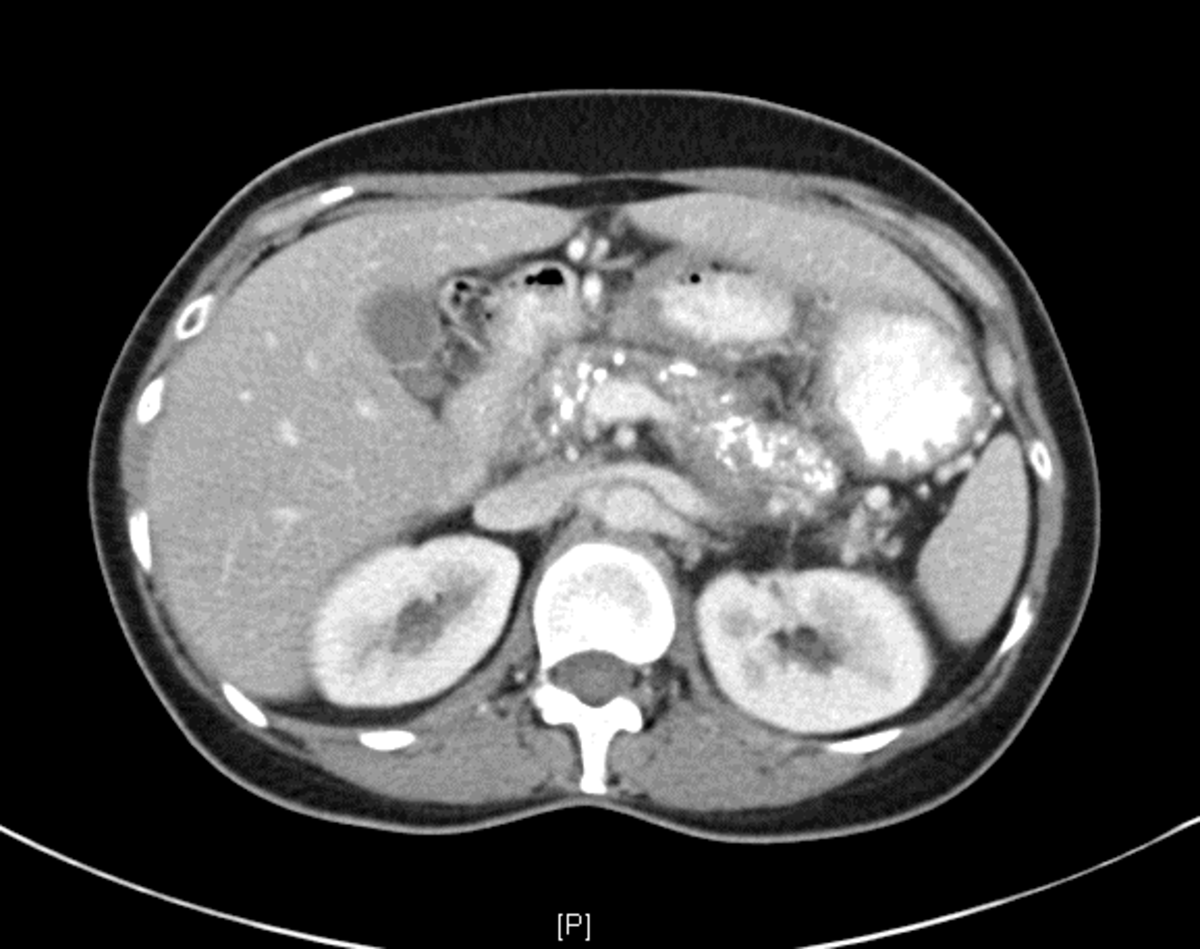

A 63-year-old woman presenting with painful calcific chronic pancreatitis (CP) is referred for further management of her abdominal pain. She has undergone noninvasive medical therapy including antioxidants, pregabalin, oxycodone, and PERT. She has managed to discontinue smoking, but the pain continues. CT scan is shown in the figure. Which of the following would be best for long-term (5 years) management of CP pain?

• This is a patient with chronic pain in the setting of CP and CT shows a dilated, irregular main pancreatic duct with calcific parenchyma disease.

• Surgery is superior to endoscopic intervention at providing longer term pain relief in CP in this setting. One RCT reported in a 79-month follow-up period, 1 patient was lost and 7 died from unrelated causes. Of the patients treated by endoscopy, 68% required additional drainage compared with 5% in the surgery group (P = .001). Hospital stay and costs were comparable, but overall, patients assigned to endoscopy underwent more procedures (median, 12 vs 4; P = .001).

• Moreover, 47% of the patients in the endoscopy group eventually underwent surgery. Although the mean difference in Izbicki pain scores was no longer significant (39 vs 22; P = .12), surgery was still superior in terms of pain relief (80% vs 38%; P = .042). Levels of quality of life and pancreatic function were comparable.